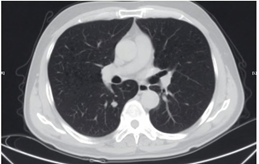

如果没有上述症状,则形状规则、边缘光滑更适合观察。肺结节的位置也很重要!肺门中央附近的结节应高度重视。一旦它们长大,手术的难度就会显著增加,甚至无法切除。(图8)

中肺周围结节的手术切除更容易,更适合观察。

中胸膜附近的结节易于去除,对肺组织的影响很小。